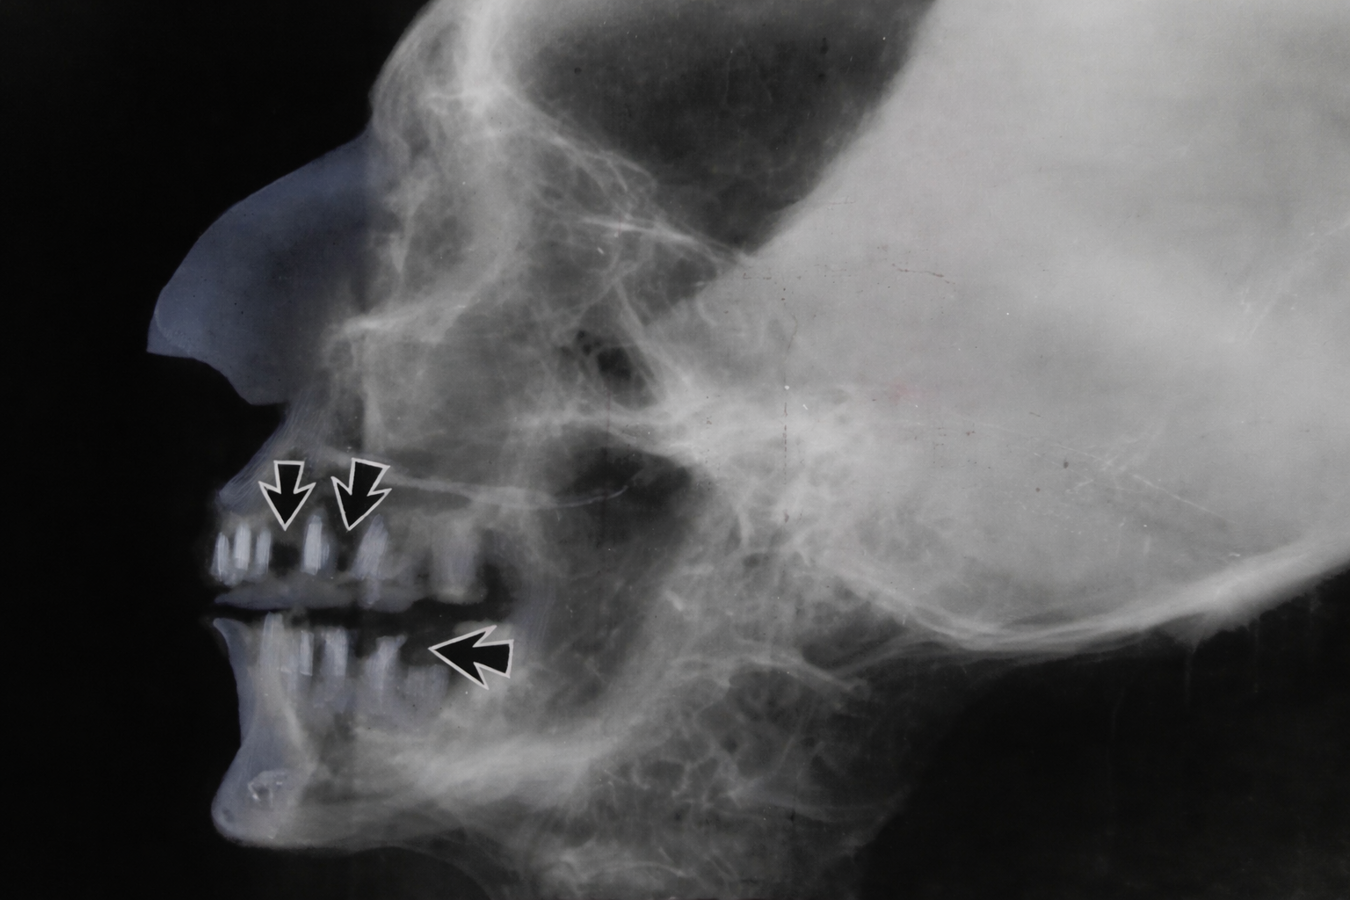

Los estudios radiológicos y tomográficos realizados a la momia de Tutankamón han permitido examinar con cierto detalle su dentición. Las imágenes obtenidas mediante tomografía computarizada muestran incisivos superiores ligeramente protruidos, lo que sugiere una forma leve de maloclusión que probablemente contribuía a una apariencia facial con labios algo prominentes y un perfil maxilar adelantado. Este rasgo ha sido descrito también en otros miembros de la familia real de Amarna y podría estar relacionado con el alto grado de consanguinidad dinástica característico de esta línea de faraones.

A pesar de la protrusión dental, los análisis no evidencian intervenciones odontológicas complejas ni prótesis dentales en el caso del joven faraón. El desgaste dental observado es moderado y consistente con la dieta egipcia de la época, rica en partículas abrasivas provenientes del pan elaborado con granos molidos en molinos de piedra. Estos hallazgos confirman que, aunque las enfermedades dentales eran comunes en el antiguo Egipto, en el caso específico de Tutankamón no se identificaron patologías orales graves que pudieran haber tenido un papel directo en su muerte.

En 2005, el Consejo Supremo de Antigüedades de Egipto, bajo la dirección del arqueólogo Zahi Hawass, realizó un escaneo completo mediante tomografía computarizada de la momia de Tutankamón. Este estudio generó más de 1700 imágenes de alta resolución que permitieron examinar con gran detalle diferentes estructuras anatómicas, incluyendo el cráneo, la dentición, la columna vertebral, la pelvis y los huesos largos. El análisis de estas imágenes proporcionó información fundamental sobre la condición física del joven faraón y permitió descartar la antigua teoría que sugería que había sido asesinado mediante un golpe en la cabeza, una hipótesis que había sido planteada por algunos investigadores décadas antes basándose en interpretaciones de estudios radiológicos previos.

Estudios con tomografía computarizada utilizados para investigar patologías dentales en momias egipcias. Foto: Shutterstock

Otros investigaciones se ha hallado evidencia de que en muchos individuos el desgaste alcanzaba la cámara pulpar, favoreciendo la aparición de infecciones dentales y por ende de abscesos. Los estudios radiográficos de momias han confirmado numerosos casos de abscesos periapicales, pérdida ósea alveolar, infecciones maxilares, terceros molares impactados, entre otras patologías. Curiosamente, la caries dental era relativamente menos frecuente que en poblaciones modernas, probablemente debido a la ausencia de azúcares refinados.

El desarrollo de tecnologías modernas, como la tomografía computarizada, ha revolucionado el estudio de momias. Esta técnica permite examinar estructuras óseas y dentales sin dañar los restos humanos12. Gracias a estas investigaciones se ha confirmado la presencia de infecciones dentales severas en numerosas momias. El estudio de momias reales ha proporcionado información particularmente valiosa sobre la salud oral de la élite egipcia. El faraón Ramsés II presentaba desgaste dental severo y múltiples abscesos periapicales según estudios radiológicos modernos11.